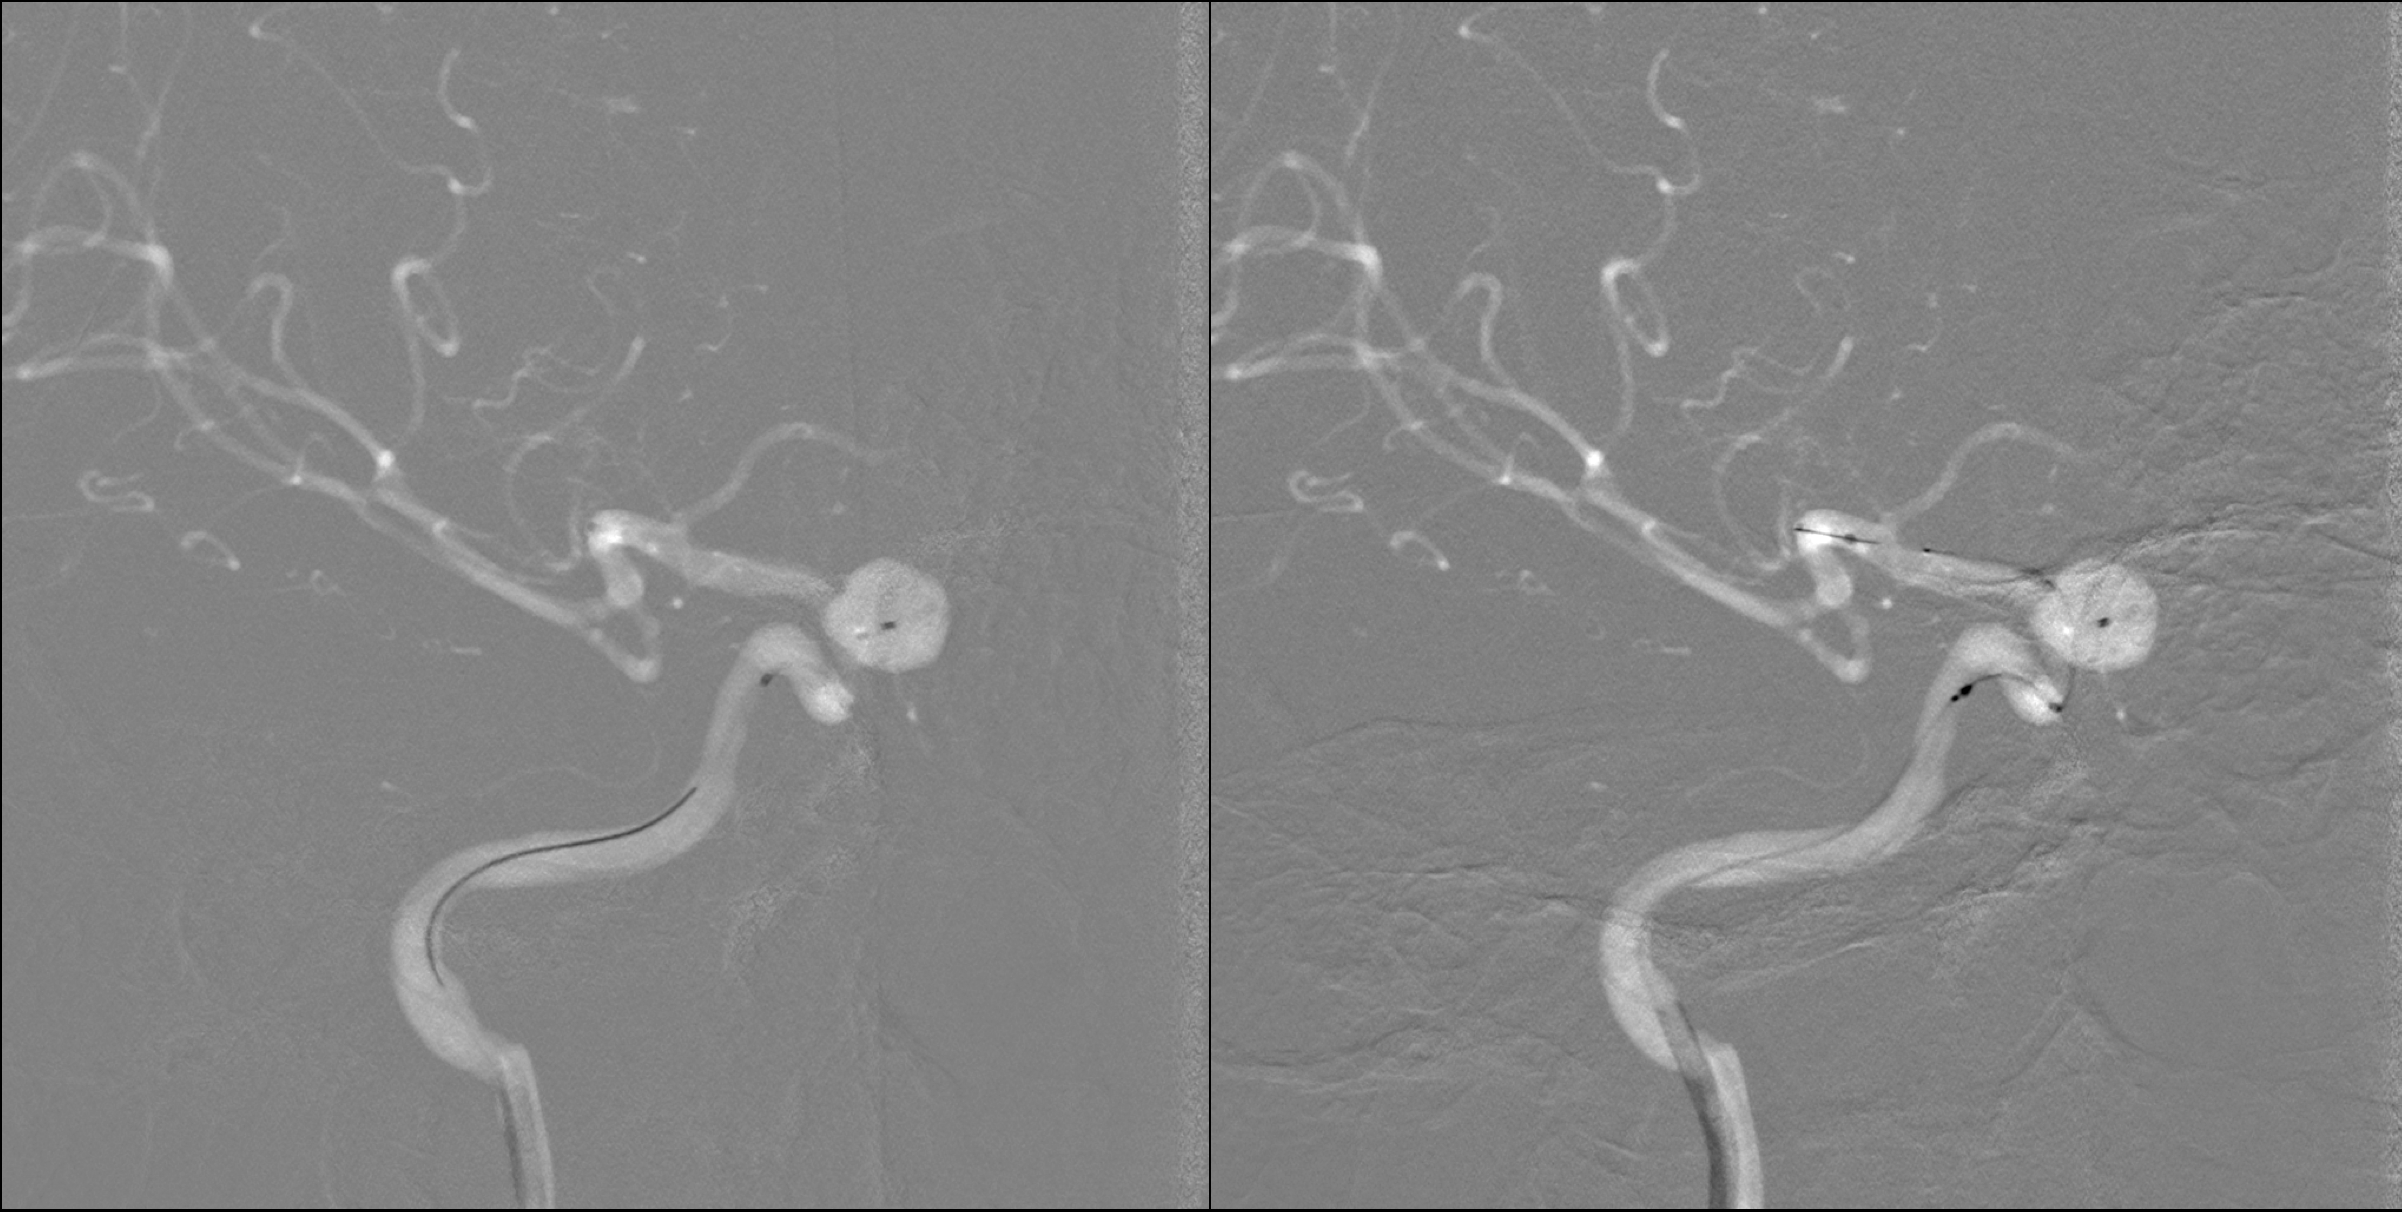

不同工作位造影:动脉瘤完全栓塞,载瘤动脉通畅。

术后正位造影及蒙片显示:动脉瘤完全栓塞!

术后侧位造影及蒙片显示:动脉瘤完全栓塞!